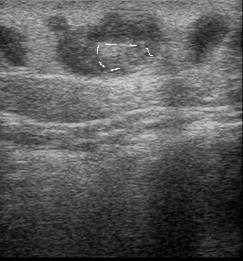

Особенно актуально это при подозрении на тромбоз глубоких вен. Существуют два прямых признака

венозного тромбоза по узи: внутрипросветные включения и некомпрессируемость (несжимаемость)

датчиком.

и функционирует. Свежий тромб по эхоплотности не отличается от обычной крови, лишь другие признаки

говорят о тромбозе. По прошествии времени, он уплотняется, и по эхогенности уже превышает таковую

жидких сред.